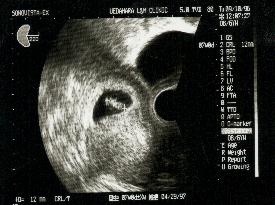

あかちゃん(胎児)の成長(妊娠7週)

あかちゃんは棒のように見え始め約10mmくらいです。

小さくても心臓はしっかりと動いているのが見えます。